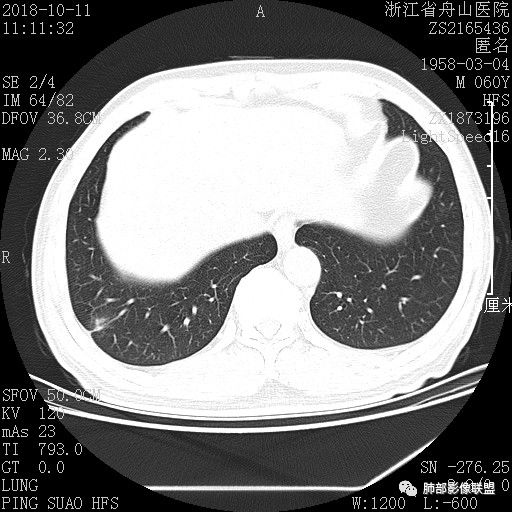

肺隐球菌病1例CT影像

男性,60岁,公务员常规体检发现肺结节20天,要求复查。 医学百科网 | YxBaike.Com

检查:一般可,两肺呼吸音清,未闻及干湿罗音。血常规(-)。 医学百科网 | YxBaike.Com

这个病人是门诊快结束时候来的,CT结果很奇怪,胸膜下实性结节,整体呈椭圆形,长轴与血管平行,有血管进入,但无分叶毛刺,基底比较窄,胸膜有粘连,有胸膜凹陷征,但是整体病灶有些“糊”。诊断上首先会想到炎性病变,询问病史和体检血象情况,均无急性感染病史,所以想先除外隐球菌感染!遂急查隐球菌荚膜多糖试验。一个半小时后,检查结果阳性!门诊以抗真菌治疗。